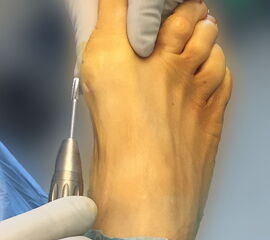

Zum Lesen der Bildbeschreibung und zur Vollansicht bitte das Bild anklicken.

• Turbine für minimalinvasive Fußchirurgie (Drehzahl ca. 2000-5000 RPM und Drehmoment 80 N/cm).

• Konische Fräse (Wedge burr 13 mm / 4,3 mm Ø).

• Gerade Fräse (Straight burr 13mm / 2mm Ø) Shannon recta 2.0.

Zum Lesen der Bildbeschreibung und zur Vollansicht bitte die Bilder anklicken.